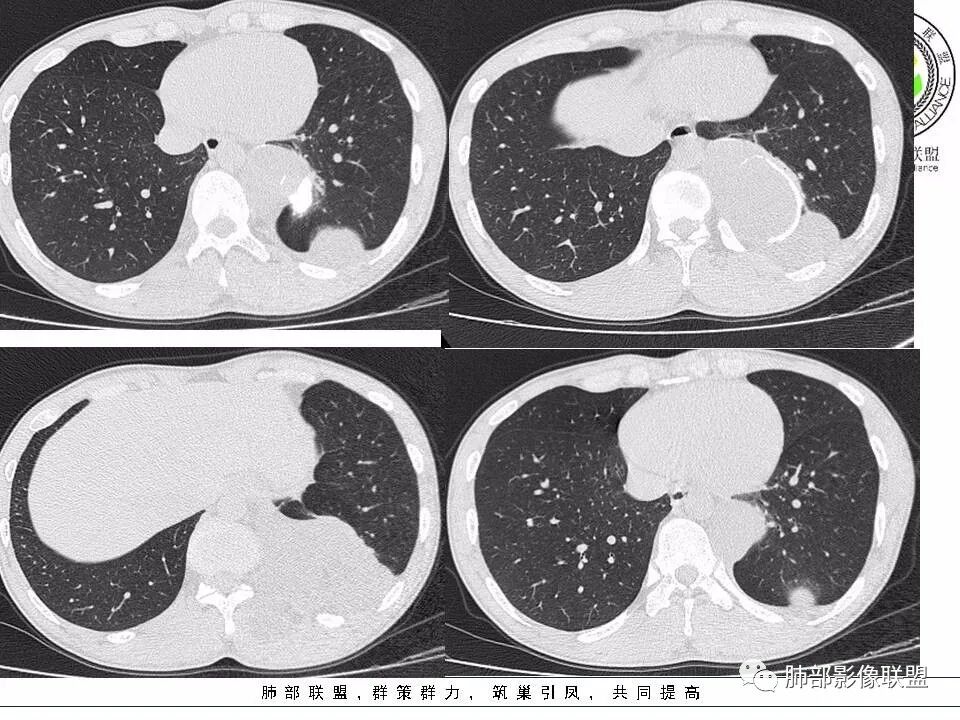

丽:

青壮年男性,背部包块一年近期明显增大,左后纵隔脊柱旁团块状混杂密度影,不规则生长,边缘可见钙化,内可见脂肪组织,邻近竖脊肌受累,短期迅速长大,考虑畸胎瘤恶变?

小兜:

左后纵隔多放囊性占位,边界清晰,内部密度不均匀,可见脂肪密度,边缘见钙化,左侧竖脊肌受累,邻近椎体及椎间盘未见破坏,考虑为良性病变,畸胎瘤,神经源性肿瘤可能

月亮圆了!:

左侧后纵隔及胸腔多房性囊性肿物,边缘可见蛋壳状钙化,考虑畸胎瘤,

三个石头:

病灶与肺组织界面清晰,脊柱旁纵隔内不规则囊性占位,边缘(包膜?)钙化,蛋壳样应该是一个特点,脂肪,肌肉累及,考虑畸胎瘤可能。鉴别结核,如果是寒性脓肿,长轴生长符合,但是椎体没有病变,结核可以这样钙化吗?这里也有神经源性,淋巴管来源病变,囊性占位,是不是都得鉴别一下啊

毛勤香:

左后纵膈脊柱旁稍低密度肿块,多房,有钙化,类似包膜钙化,含脂,向胸壁外突出,邻近骨质无破坏和增生,左侧椎间孔似略扩大,年轻男性,肿块感觉偏软,穿刺有红细胞,定性良性或低度恶性,首先考虑畸胎瘤,鉴别神经节细胞瘤和脉管瘤。

采莲:

青年男性,左下靠近脊柱旁,多发软组织肿块,一个靠近主动脉旁,有钙化,一个在左下胸膜下,一个在肌肉里面,考虑来源胸膜下,考虑侵袭性纤维瘤?神经源性肿瘤?

飞鹰行动:

青年人,左侧下胸腔可见不规则肿块影,病灶向竖脊肌侵袭,病灶边缘可见弧形钙化,内可见分隔样改变及脂肪密度,首先考虑畸胎瘤,其次节神经细胞瘤。

一切∮随缘:

左肺胸膜下肿块,部分向肋骨外及纵隔生长,边缘膨隆,与胸膜宽基底,密度不均匀,边缘可见弧形钙化,并可见脂肪密度,无增强,考虑:1:畸胎瘤2:错构瘤3:脂肪瘤